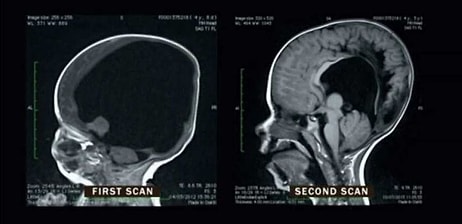

9. Случай столбняка у непривитого ребенка